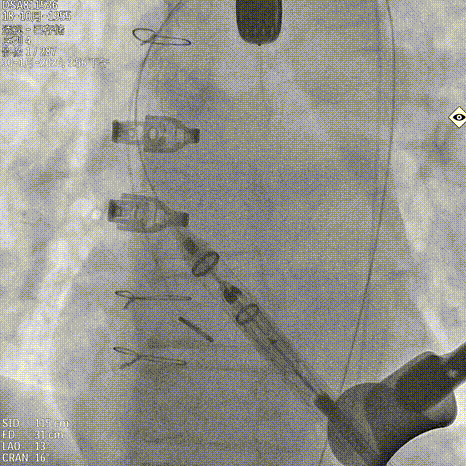

基于瓣环及瓣上结构的锚定条件,手术团队选择 JS/TAVI-31 瓣膜进行植入。术中团队配合默契。鉴于主动脉瓣上空间有限,手术在瓣环位置释放定位件后送入瓣上并尝试入窦。得益于输送器独特的调弯设计,仅经两次尝试即顺利进入窦内并完成瓣膜释放,器械操作时间仅 8 分钟。手术过程中,团队通过右冠窦居中造影、定位件入窦确认,以及释放后超声联合造影评估,多重手段保障瓣膜定位精准、释放过程平稳,整体手术流程按术前预演顺利完成。术中超声评估未见瓣周漏,血流动力学表现良好,手术顺利结束。

造影确认右窦居中位置

释放定位件尝试入窦

输送系统进行调弯

造影第一次未完全入窦

调整再次入窦

造影确认定位件入窦底

释放瓣膜